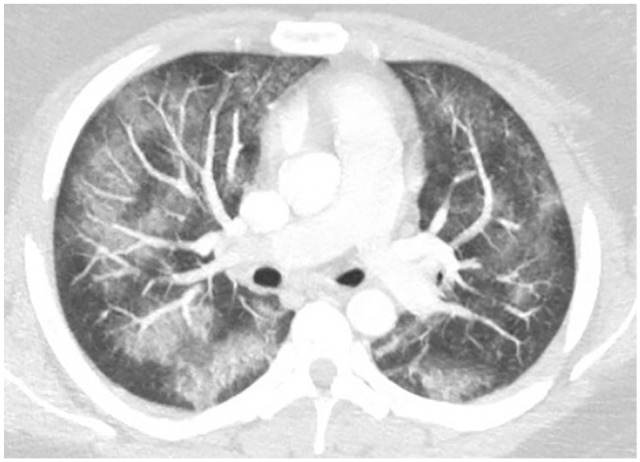

She returned to the emergency room the following day with progressively worsening shortness of breath. Her RR was 24 breaths per minute and saturating 84% on room air. Computed tomography angiogram (CTA) of the chest with and without contrast revealed bilateral patchy ground glass opacities within the bronchovascular distribution (Figure 1). The patient’s clinical condition deteriorated over the next 12 hours requiring high-flow oxygen and repeat imaging showed worsening bilateral pulmonary opacities. On further questioning, the patient admits to smoking marijuana, which she switched to vaping with CBD/THC oil 2 months prior to this presentation, which she bought off the street. She never smoked cigarettes. She denied having any pets, recent travel history, or exposure to any sick contacts. Laboratory workup was significant for leukocytosis, elevated erythrocyte sedimentation rate (ESR), C-reactive protein (CRP), procalcitonin, and urine drug screen was positive for cannabinoids/THC (Table 1). Airway examination was normal on bronchoscopy and bronchoalveolar lavage (BAL) gram stain showed mixed respiratory flora and cultures were negative bacterial, fungal, and viral pathogens. BAL differential showed 5% neutrophils, 10% lymphocytes, and 85% macrophages. Antibiotics were escalated to ceftriaxone and azithromycin for 5 days. She also received methylprednisone 60 mg daily × 3 days, then changed to oral prednisone 40 mg daily with a tapering course of 10 mg per week over a 4-week period. A presumptive diagnosis of VALI secondary to vaping CBD/THC was made as the patient responded very well to the steroids. Her symptoms significantly improved and was discharged home 7 days later without the need for supplemental oxygen.